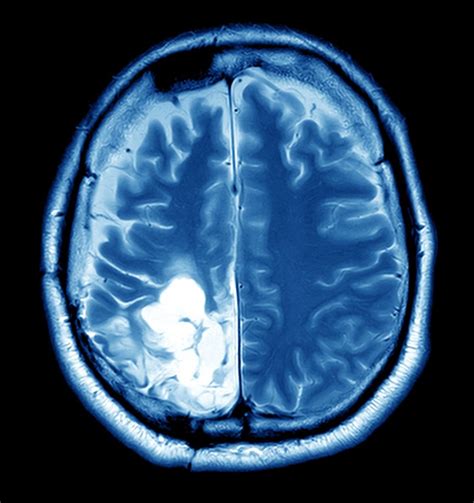

• Imaging Tests: Imaging tests such as X-rays, CT scans, MRI scans, and PET scans can help visualize the tumor or tumour and determine its size, location, and extent.

• Biopsy: A biopsy involves removing a small sample of tissue from the tumor or tumour for examination under a microscope. This can help determine whether the tumor or tumour is benign or malignant.